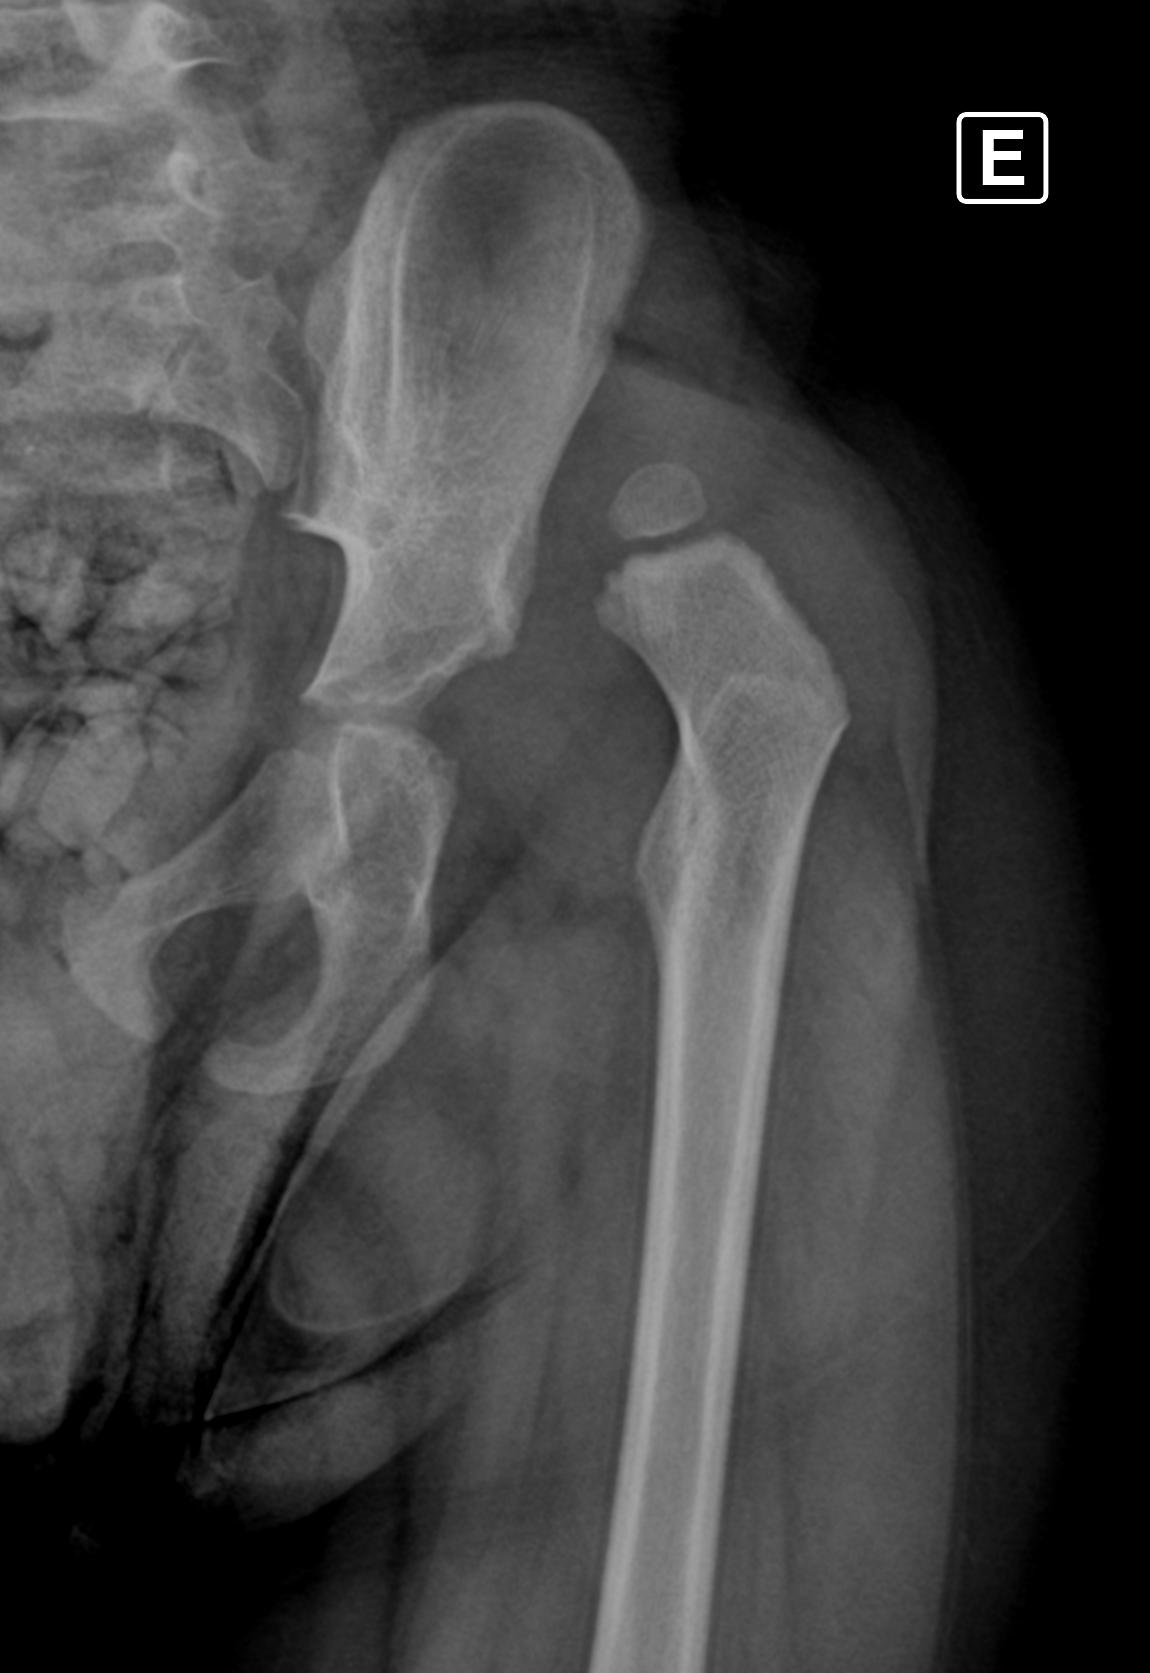

Aos três anos, o pequeno Heitor Henrique Moraes de Oliveira enfrenta uma difícil batalha contra a displasia coxofemoral — uma luxação congênita no quadril esquerdo descoberta quando ele tinha apenas um ano. A mãe, Camila Moraes, contou que percebeu algo errado quando o filho demorou a caminhar:

“Desde a primeira consulta em Santo Ângelo, a ortopedista nos disse que seria necessária uma cirurgia. Ficamos na fila do SUS, mas graças a Deus conseguimos adiantar o procedimento devido à urgência, pois a situação poderia piorar conforme ele crescesse,” relatou.